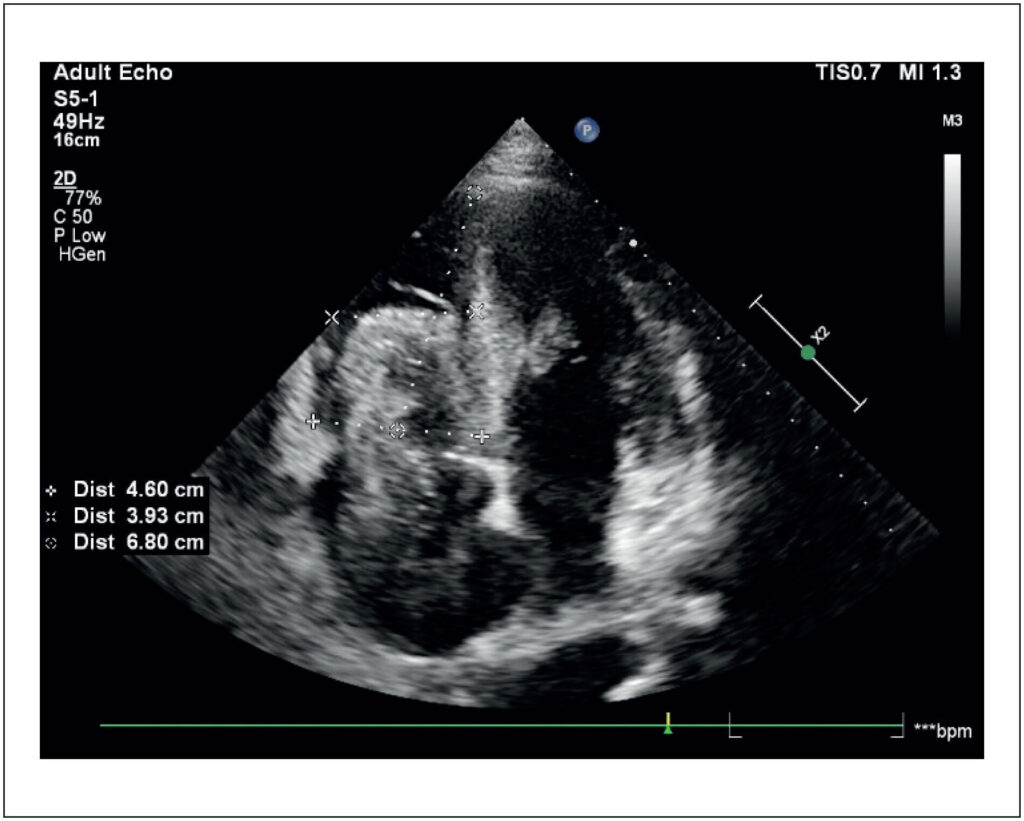

O carcinoma de células renais (CCR) é um dos cânceres mais letais, frequentemente associado à formação de trombos tumorais (TT), uma extensão intravascular do tumor. Aproximadamente 4% a 10% dos pacientes com CCR apresentam TT, que pode atingir a veia renal (10% a 18%), a veia cava inferior (4% a 23%) e, raramente, o átrio direito (1%). Esses trombos geralmente acompanham tumores avançados, com metástases à distância, e refletem uma biologia agressiva. O tratamento é desafiador, especialmente em casos metastáticos, sendo a ressecção cirúrgica indicada na ausência de metástases. A anticoagulação permanece controversa devido à composição neoplásica dos TT. Relatamos o caso de um homem de 51 anos com CCR de células claras e metástases pulmonares e hepáticas, tratado com pazopanibe. O paciente apresentou insuficiência cardíaca direita e foi diagnosticado com TT extenso até o átrio direito, identificado por ecocardiograma transtorácico. Em estágio avançado e com deterioração clínica, optou-se por cuidados paliativos, evoluindo a óbito em poucas semanas. O diagnóstico de TT é crucial para definir o prognóstico e as estratégias terapêuticas. O ecocardiograma, combinado a técnicas avançadas de imagem, tem papel fundamental na diferenciação entre TT e tromboembolismo. Este caso ressalta a importância da abordagem multidisciplinar e de avanços tecnológicos para o manejo de condições complexas como o TT, visando diagnóstico precoce e redução de complicações.